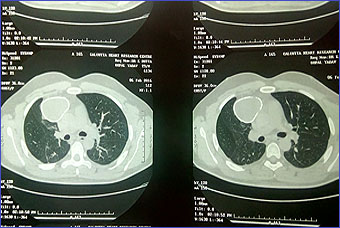

Case 1

A 30 years old male presenting with low grade fever and cough with scanty mucoid expectoration and streaky hemoptysis for last one year. His complaints was subsided with oral co amoxiclav and cough suppressant. He has no chest pain or shortness of breath. Past history revealed tubercular pleural effusion at 4 years of age with ATD completed then. He remained asymptomatic for last 26 years. His chest x-ray and CT scan chest given. Mantoux test is positive showing 10mm induration. His echinococcus IgG is positive in high titre.